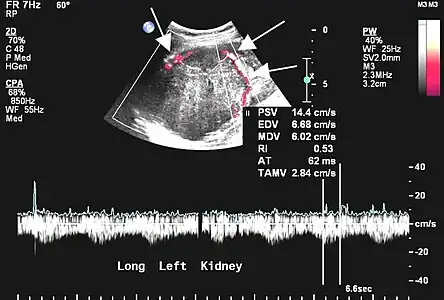

Aspect échographique. La vascularisation est visible en rouge, repérée par les flèches[46].

L'échographie est rarement réalisée pour les localisations pleurales, mais peut être utile dans les autres localisations[45]. Les tumeurs fibreuses solitaires se présentent comme des masses homogènes, hypoéchogènes et bien délimitées ; le doppler permet de visualiser la vascularisation. Les tumeurs pleurales se mobilisent avec les mouvements ventilatoires[45].